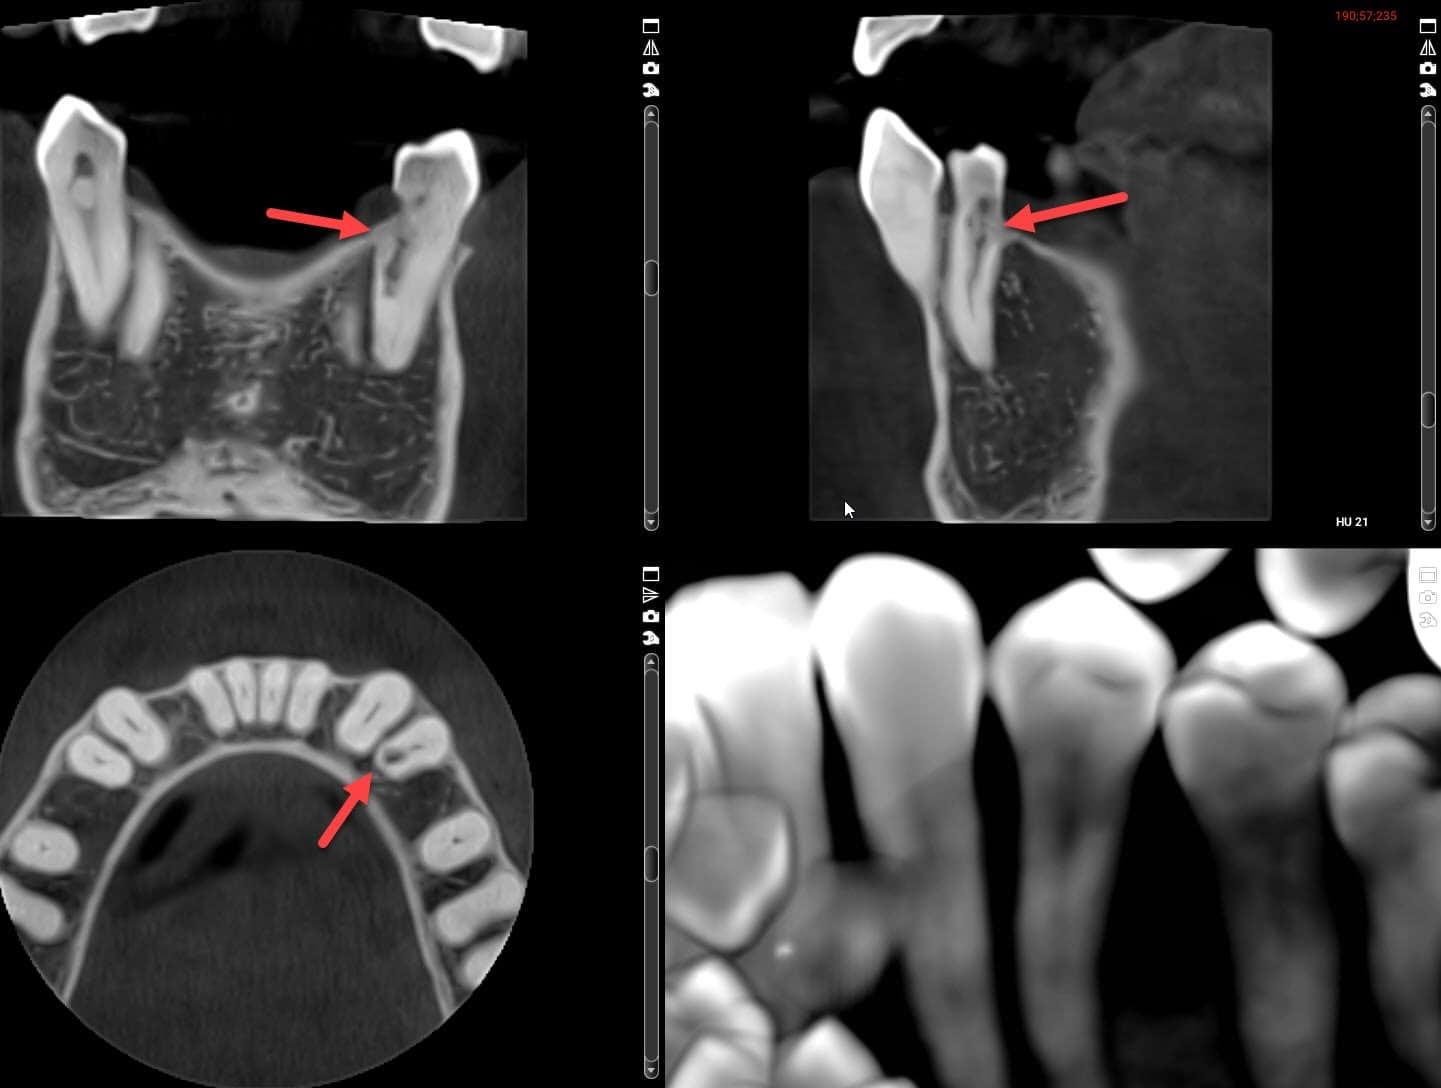

Based on this x-ray alone, I didn’t know if this was internal or external resorption. So we took a 3D Cone Beam x-ray , to see it from multiple angles, as seen below. From that, it appears to be internal root resorption. It got big enough to break through the root, which allows bacteria in. That’s probably why it became sensitive recently.

We don’t know yet if this tooth can be saved, but I’ve referred her to a root canal specialist (endodontist) and gum specialist (periodontist). If they can’t save it, we will probably do a dental bridge to replace the tooth. The other tooth roots are too close together for a dental implant. I’ll try to remember to update the post once she makes a decision.

As I mentioned, root resorption is pretty uncommon. In my 20+ years of practicing dentistry, I’ve only come across a few cases. That’s why the patient in the first case above was so unusual. When evaluating the lower front tooth resorption, I noticed a second tooth with resorption, but this time it clearly started outside of the tooth. 2 teeth with resorption on the same patient is odd enough. One tooth with internal resorption and one tooth with external resorption on the same patient??? I’ve never seen, nor even heard of that happening.

It’s a good thing we took the 3D Cone Beam x-ray on the patient though, because we couldn’t see it on the regular bite-wing x-ray at all. This tooth didn’t bother her at all, so we had no reason to suspect it.

Unfortunately, this tooth is definitely not fixable, so it will be extracted and probably replaced with a dental implant and crown. Since it isn’t bothering her and isn’t visible in her smile, we’ll wait until the other tooth is finished.